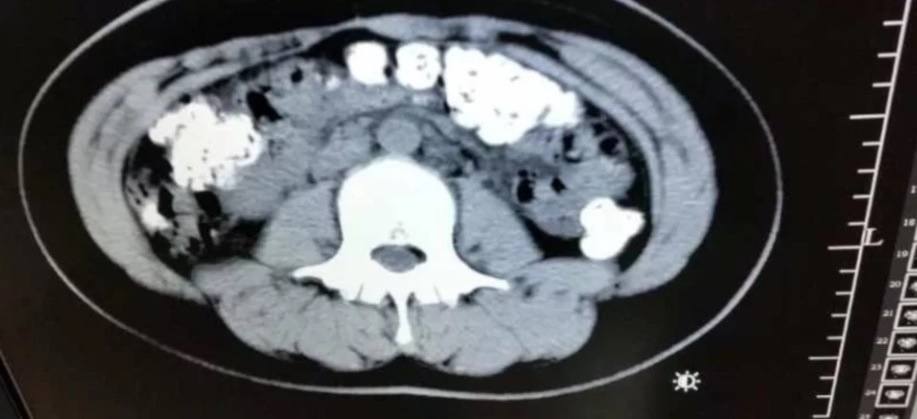

gif_animation 国内でも話題になっていますが、当サイトでも一応紹介。中国にて、腹痛・便秘を訴え病院を訪れた14歳の少女。その腹部をCTスキャンで撮影した所、胃や腸の中に100個以上の消化されていないタピオカが残されていたとの事。原因はタピオカに含まれる防腐剤などの添加物が胃腸障害を引き起こしたため。これは怖い。[3]images

※ 14歳の少女、CTスキャン